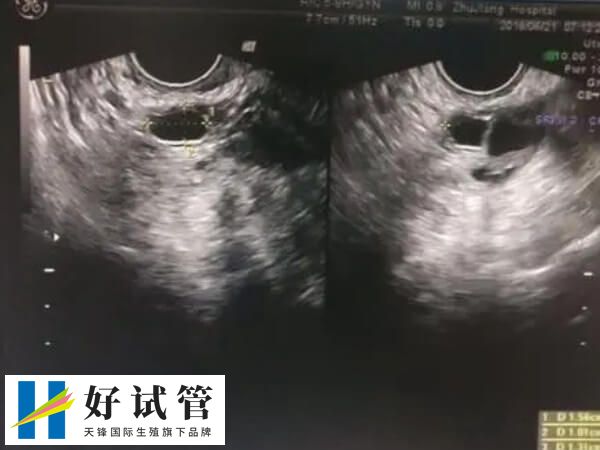

人工授精过程中需严格无菌操作,避免精液或阴道分泌物传播病毒。若滴度未达标,可能导致胎儿先天性梅毒、流产或畸形。所以梅毒女人可以做人工授精前,需要满足以下条件。

- 1、滴度要求∶需完成规范治疗(如青霉素疗法),非梅毒螺旋体抗体滴度(RPR/TRUST)需稳定在≤1:2的低水平,且连续3次复查(间隔3个月)无波动,表明无活动性感染和传染性;

- 2、治疗时长∶早期梅毒需2-3周治疗,晚期可能需3-6个月,治疗后需观察1-2年确认无复发。